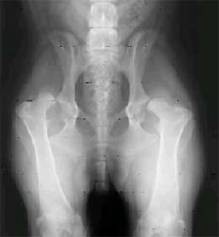

Krankheiten - Hüftgelenkdysplasie (HD)

Der Fachausdruck Dysplasie bedeutet eine Fehlentwicklung, Unterentwicklung des Skeletts, durch welche der Bewegungsapparat eingeschränkt wird. Die Gelenkspfanne und der Oberschenkelknochen passen nicht korrekt aufeinander. Die aus dieser Fehlbildung entstandenen Knorpelablagerungen (Artrose) verursachen in fortgeschrittenem Stadium Schmerzen.

Bedeutung der Röntgen-Resultate von HD (HD-Grade)

A = frei von Dysplasie - normales Hüftgelenk       = zuchttauglich

B = Übergangsform                    &                       = zuchttauglich

C = leichte Dysplasie                                         = nicht zur Zucht empfohlen

D = mittelgradige Dysplasie                                = von der Zucht ausgeschlossen

E = hochgradige Dysplasie                                  = von der Zucht ausgeschlossen